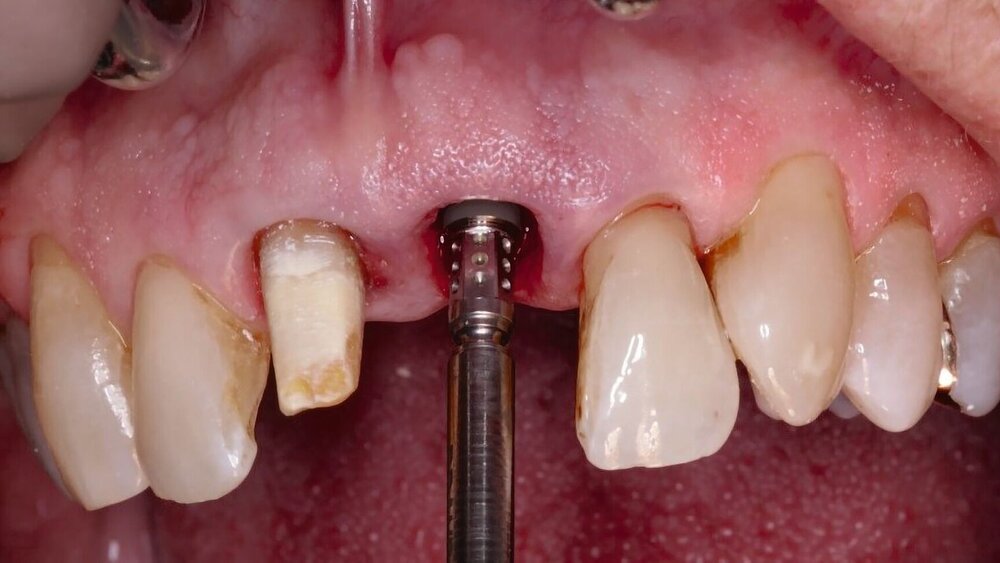

Technisches Vorgehen bei der Sofortimplantation

Die Vorhersagbarkeit des Implantaterfolgs bei der Sofortimplantation ist abhängig von der lokalen Ausgangssituation. Dabei ist die Qualität und Quantität der Hart- und Weichgewebe von zentraler Bedeutung. So ist es klinisch plausibel, bei der Zahnextraktion das Trauma auf das Weich- und Hartgewebe so gering wie möglich zu halten [Gamborena et al., 2021]. Ein operativer Zugang ohne Bildung eines Mukoperiostlappens („Flapless“) scheint einen positiven Effekt auf die Knochenstabilität zu haben [Lin et al., 2014; Zhuang et al., 2018]. Der Verzicht auf die Bildung eines Mukoperiostlappens erschwert jedoch gleichzeitig die lokale Beurteilbarkeit der knöchernen Situation. Inwieweit ein invasiverer Zugang bei der Sofortimplantation gewählt werden sollte, ist im Einzelfall zu diskutieren. Neben den lokalen Faktoren ist entscheidend, ob und welche augmentativen Maßnahmen simultan bei der Implantatinsertion geplant sind.

Des Weiteren ist die Primärstabilität ein entscheidender Faktor für die Osseointegration des Implantats [Meredith, 1998]. Ist durch lokale Pathologien oder anatomische Gegebenheiten nicht ausreichend Restknochen nach der Zahnextraktion vorhanden, um das Implantat in der korrekten 3-D-Ausrichtung primärstabil inserieren zu können, sollte von einer Sofortimplantation abgesehen werden [Hammerle et al., 2004; Chrcanovic et al., 2017; Cosyn et al., 2019; Tonetti et al., 2019]. In einer Metaanalyse konnte die Implantatposition als eigenständiger Risikofaktor für die Entstehung von vestibulären Rezessionen bestätigt werden [Hammerle et al., 2012]. In der Oberkieferfront wird eine palatinale Implantatposition angestrebt [Kan et al., 2018].

Die Sofortimplantation stellt hinsichtlich der korrekten dreidimensionalen Position und Stabilisierung in der Extraktionsalveole eine besondere Herausforderung dar. In der Oberkieferfront sollte die achsengerechte und positionsgerechte Implantatinsertion palatinal orientiert sein. | starker Konsens |